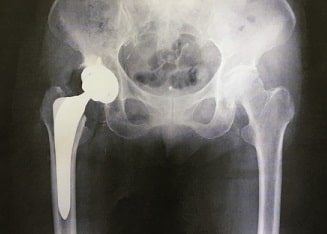

全身のステロイド療法によって、大腿骨頭壊死、上腕骨頭壊死、距骨や舟状骨の壊死などがおこります。

なぜか原因がわからないのに大腿骨の骨頭壊死になってしまった方、ステロイド薬を何らかのかたちで使用していませんでしたか。